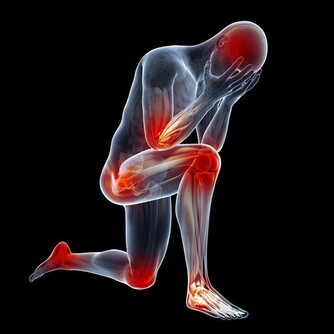

經常久坐的人,患上頸椎病的概率會更高。因為人體的骨連接需要足夠的黏液,來保證關節的正常使用。而久坐的人產生的黏液較少,會使骨關節變得乾燥,久而久之會引發頸椎病和關節炎。

此外,長時間保持一個姿勢不動,還會對頸椎動脈供血造成影響,並破壞人體正常生理彎曲,導致駝背和骨質增生。

數據顯示,如果每天久坐超過3個小時,那麼就會減慢人體靜脈血液的流速,容易形成血栓,增加罹患心腦血管疾病的機率,誘發冠心病。久坐還會阻礙大腦的正常供血,長期下來易出現失眠、嗜睡、記憶力下降等情況,甚至引起老年癡呆症。

另外,對於本身患有動脈硬化的中老年人來說,還會加大腦血栓和心肌梗塞發生的風險。